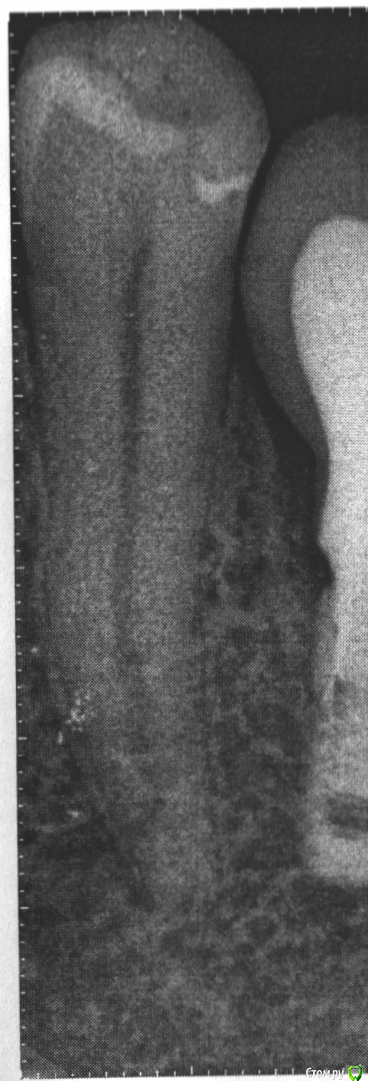

Megazub Опубликовано 30 сентября, 2020 Автор Поделиться Опубликовано 30 сентября, 2020 Вот снимок. Снимок распечатали на бумаге, а не на пленке. Ссылка на комментарий

red_butler Опубликовано 1 октября, 2020 Поделиться Опубликовано 1 октября, 2020 А со снимком то что? на снимке все нормально Ссылка на комментарий

Megazub Опубликовано 2 октября, 2020 Автор Поделиться Опубликовано 2 октября, 2020 Что вас беспокоит касательно зуба? После лечения, зуб стал сильно реагировать на холодное и сладкое, а также на надавливание в определенной точке зуба. на снимке все нормально почему тогда может болеть? Ссылка на комментарий